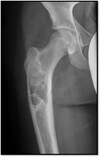

Legg–Calvé–Perthes disease | Femoral head dying because of avascular necrosis

167

What pathology is seen here?

Legg–Calvé–Perthes disease | Left femoral head is flatter and shorter than the typical femoral head